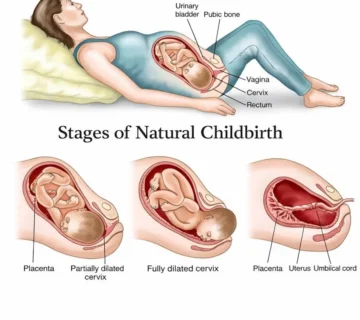

During week 10, your baby’s internal organs are coming to life. A routine ultrasound may show that the yolk sac has disappeared and the umbilical cord, which connects the placenta to your baby, is now fully visible.

The intestines, still partly inside the cord, are moving gradually into the abdomen and will soon be covered by skin. Meanwhile, several vital organs start functioning:

Your baby’s lungs are developing, and tiny bones—even within the fingers—are forming. Bone marrow cells will soon start producing red blood cells, a task previously handled by the liver and spleen.